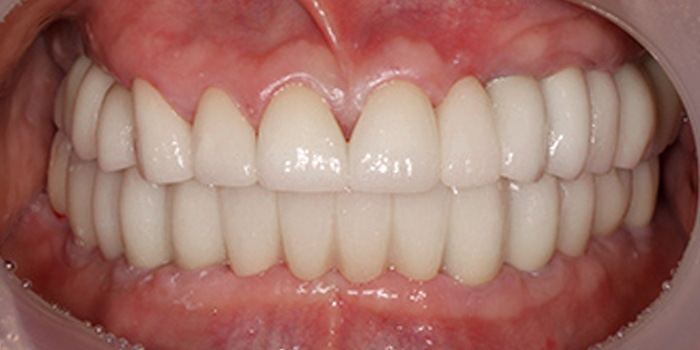

05 60대 남성, 기존 임플란트 부작용으로 재수술, 치료기간 6개월